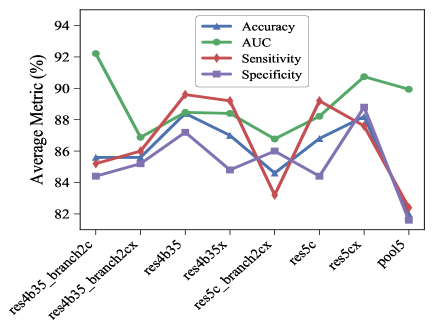

For all these experiments, we found that taking features from earlier layers compared to later layers improve accuracy by 2 to 4 percentage points. Shallow DCN features are often useful for detecting small objects in images [27]. Our findings are similar for chest X-Ray abnormality classification as well. As an example, we are showing the performance obtained by taking features from different layers of ResNet-152 model. The candidate layers are chosen from the 4th, 5th and final stage of the network based on what type of operations they perform. The chosen layers and their corresponding operations are listed in Table 3. The notation of the layers is based on the pre-trained model obtained from MatConvNet Pre-train Library. We trained five models to detect cardiomegaly using features from each of the layers and the average performance of these features in terms of accuracy, AUC, sensitivity, and specificity for Cardiomegaly detection are shown in Fig. 3. It can be observed that the performance of the final pooling layer (pool5) is degraded compared to the other layers in terms of accuracy, sensitivity and specificity. In particular features from residual connections (res4b35, res5c) and ReLU (res4b35x, res5cx) are considerably better with features from res4b35 providing highest accuracy. Similar observations are made for other ResNet variants, VGG nets and AlexNet.